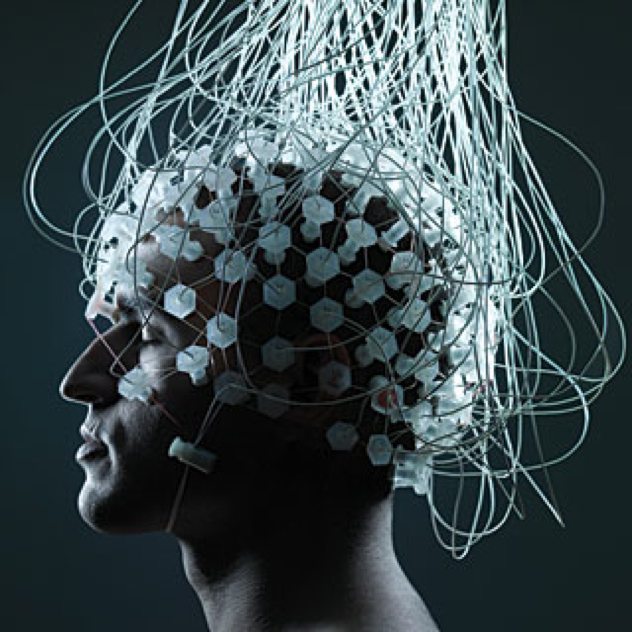

5. Công nghệ BCI

Chính xác thì đó là công nghệ giúp liên kết bộ não con người với các thiết bị ngoại vi khác. BCI đã rất phổ biến trong những phim khoa học viễn tưởng trong nhiều thập kỷ, tin hay không thì nó cũng đã được ứng dụng thực tế từ thập kỷ 90 rồi. Công nghệ hoàn toàn an toàn và có ích nên đã không ngừng phát triển cho đến nay.

Lần đầu tiên BCI được biết đến từ năm 1920 khi phát hiện ra những tín hiệu điện phát ra bởi não bộ và chúng cho phép điều khiển một thiết bị cơ khí nhỏ. Chỉ tới năm 1960 thì những nghiên cứu nghiêm túc về BCI mới được thực hiện trên khỉ và trong khoảng 15 năm trở lại đây chúng ta mới có được nhiều ứng dụng ưu việt từ nó.

Hầu hết người ta sử dụng BCI để phục hồi một phần thị lực, thính giác hoặc một bộ phận cơ thể bị tê liệt cho bệnh nhân. Năm 2013, y học đã chứng kiến một trường hợp đột quỵ bị liệt toàn thân nhưng vẫn sử dụng được máy tính thông qua những tín hiệu điện não. Một thiết bị cực nhạy nhận tín hiệu từ bộ phận điều khiển mắt trên não bộ và phân tích các tần số khác nhau để xác định bệnh nhân muốn di chuyển con trỏ tới đâu. Thiết bị đó chỉ trông giống như một chiếc mũ bảo hiểm bình thường.